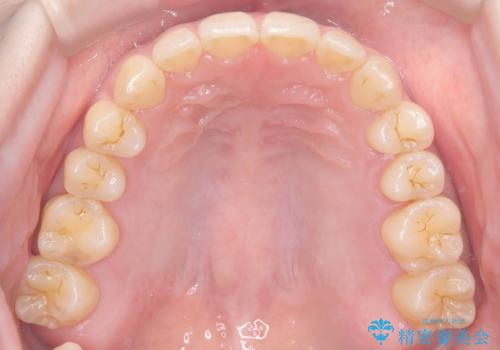

下顎前歯の叢生がとれ右上2の反対咬合も改善し患者様にも満足していただけました。治療期間は1年~1年半を見込んでいましたが、患者様の協力もあり10か月で矯正を終えることが出来ました。